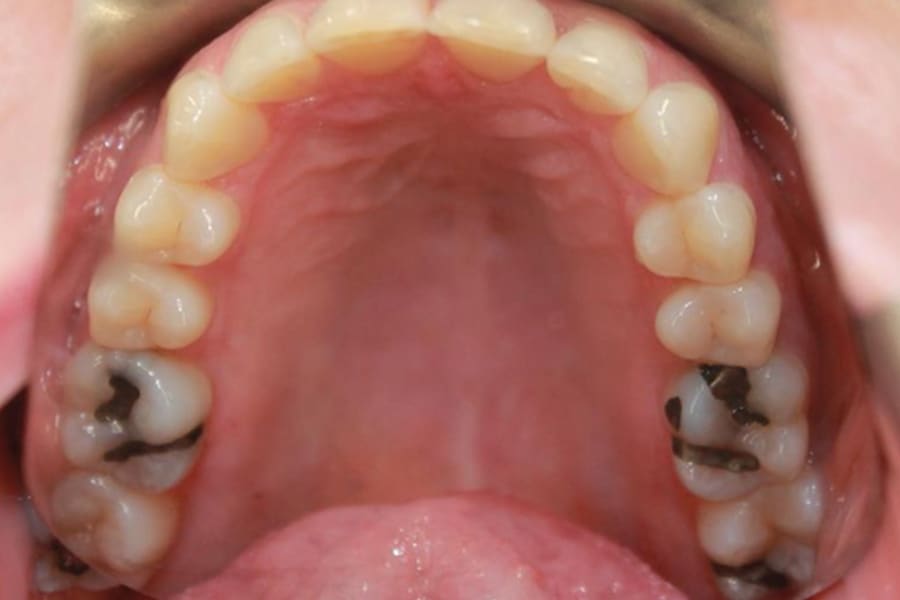

A 54-year-old woman presented with a chief complaint of teeth crowding. After comprehensive digital records were obtained, ClearCorrect® aligner therapy (Straumann, clearcorrect.com) was chosen with an anticipated 12-month treatment duration. The patient exhibited moderate anterior crowding, a class II molar relationship, and narrow arches. The treatment plan aimed to resolve the class II discrepancy, expand the arches, and establish proper anterior alignment. A total of 25 active aligners plus two retention aligners were prescribed. Attachments were selectively placed on the maxillary and mandibular canines to premolars, minimizing bulk while maintaining control over torque and posterior alignment. The patient was instructed to wear class II elastics full-time, which was crucial to achieving molar correction and arch expansion. Her outstanding compliance with class II elastics contributed to a significant improvement in molar position and transverse arch development. After completing the active phase, the patient transitioned to retainers to ensure long-term stability of the results. Given the patient’s initial class II occlusion, monitoring retention was emphasized to prevent relapse. The patient was extremely pleased with the outcome, demonstrating a broadened smile and improved occlusal function. This case underscores the effectiveness of ClearCorrect’s aligners in adult patients, particularly when combined with compliant elastic wear and targeted expansion strategies.